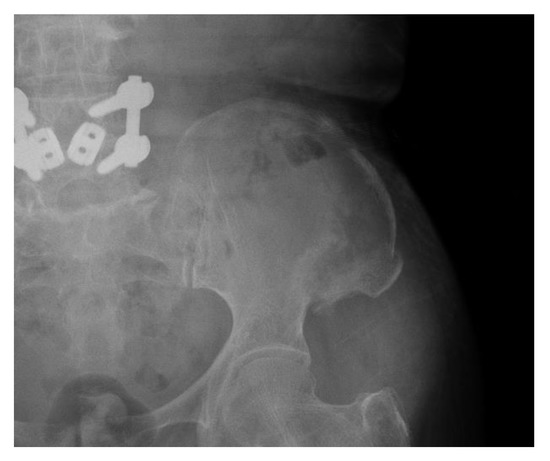

Conservative Treatment of Avulsion Fracture